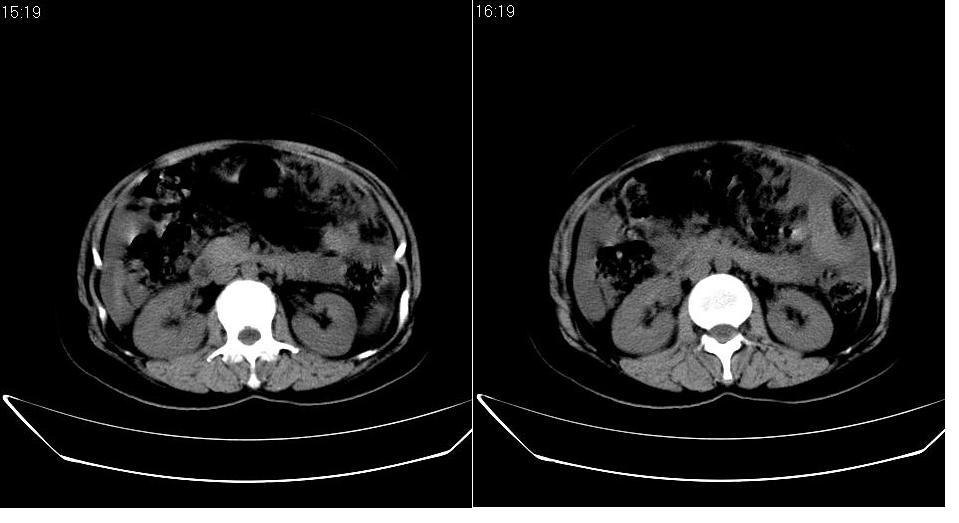

以下是引用zbp537在2009-1-19 14:09:00的发言:[br]从这个平扫图像上看,只能考虑:1、胸腹水。2、脾脏包膜下弧形高密度影,疑出血,建议复查。[br]既然腹水中有恶性细胞,建议行腹部ct增强扫描及胸部扫描。

以下是引用随光逐影在2009-1-19 15:47:00的发言:[br]1)不排除胃癌可能;建议行胃镜检查。2)腹水。3)右侧胸腔积液。

以下是引用jiangjing在2009-1-19 18:21:00的发言:[br]1 网膜污垢征---肿瘤网膜转移.2)腹水。3)右侧胸腔积液